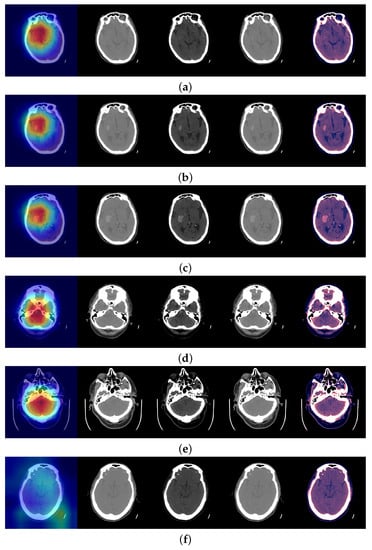

Figure 2.

The model Efficient Classification predictions were all correct. In addition, Grad-CAM was able to focus on the bleeding area to make that decision. In each image, from left to right: Grad-CAM, [0.80] window, [−20, 180] window, [−150, 230] window, the three windows stacked. From (a–f) the probabilities of ICH in the slice are 0.9897, 0.9972, 0.9997, 0.7805, 0.8101 and 0.0097.

In Figure 2a a slice with ICH is shown. It was quite difficult to see the ICH, but the Efficient Classification neural network predicted ICH with a probability of 0.9897. Figure 2b,c show the next consecutive two slices where ICH was clearly seen and the neural network predicted ICH with a probability of 0.9972 and 0.9997, respectively. Figure 2d shows a slice with ICH, where the hemorrhage was not detected, according to our threshold (0.8), and the probability was 0.7805. Figure 2e shows a positive slice where the probability was just above the threshold, 0.8101. On the other hand, in Figure 2f a slice without ICH is shown.

A typical detected minimum size of a hemorrhage (width) by Aidoc software is shown in Figure 2a of [22] and was about 2 mm. In clinical practice, there are rarely less than 25 slices per brain scan. We did not check or train the model for the size of the hemorrhage. Let us note that the model was trained on slices with yes/no for all the slices, and we did not train the model for the location of the hemorrhage. The Grad-CAM map should not be mistaken for the location of the hemorrhage. It can be interpreted as the usual location of the hemorrhages and the pixels considered in the evaluation of the presence of hemorrhages for this slice, but not as a precise location.